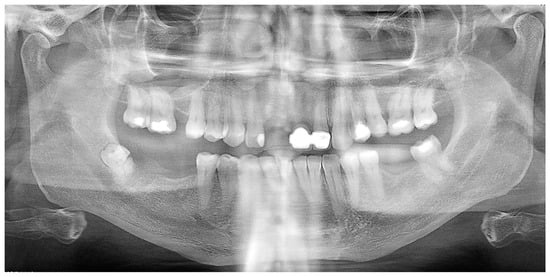

2. Detailed Case Description